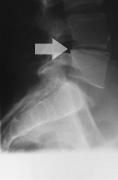

Patients who suffer from cervical radiculopathy, a condition in which a nerve is pinched within the cervical (neck) area of the spine, are typically treated with a variety of physical therapies designed to restore physical functions. Many of these therapies involve neck-specific treatments, cognitive-behavioral therapies, or anterior cervical decompression, which involves surgically removing the disc that's putting pressure on the spinal nerve.

In a randomized study conducted by researchers at several Swedish universities, sixty-three patients who suffered from radiculopathy and nerve root compression were randomized to receive either anterior cervical decompression and fusion (ACDF) in combination with physical therapy, or physical therapy alone. The objective of the study was to investigate if there were any differences in physical functional outcome. Researchers hoped that the results produced by this study would help clinicians form the best physiotherapy treatment for patients suffering from cervical radiculopathy.